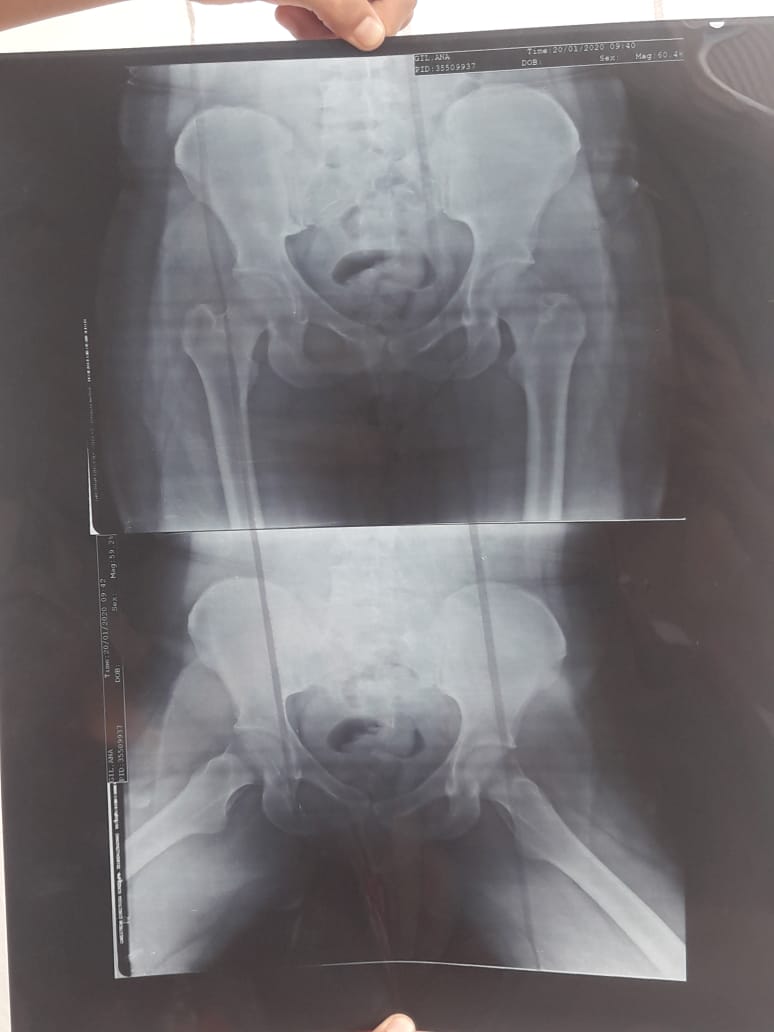

Una aneurisma cerebral le ocasionó una hemiplejia espástica que le deforma progresivamente los músculos y la posición de los huesos, generándole fuertes dolores y dificultad para caminar, entre otras cosas.

La joven oriunda de Rivadavia contó que la obra social que tiene (Incluir Salud) no le cubre la cirugía en el exterior porque el hospital donde debe realizarse la intervención está fuera de la Red Pública Nacional de Salud. “Fui a Salud Pública y me dijeron que me podían ayudar con la mitad, pero yo no tengo de donde más sacar dinero, apelo a la solidaridad de la gente o de alguna empresa que pueda ayudarme a tener una vida, es difícil pasar los días sufriendo pensando que vas a terminar en una silla de ruedas sabiendo que la cura está, existe y está en México”, comentó Ana María mientras sostenía en sus manos la última radiografía de pelvis.